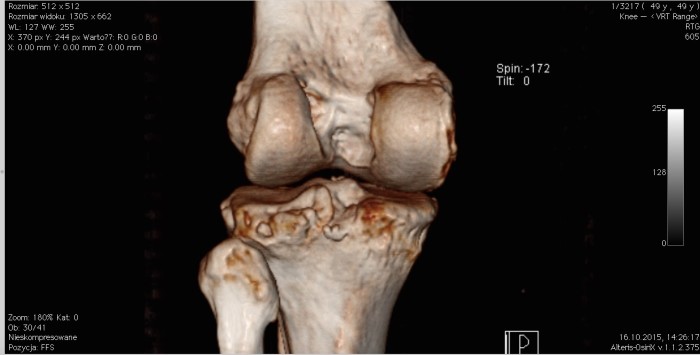

Tomograf komputerowy. Czy jest przydatny w ortopedii?

Jak już wcześniej wspomniałem TK wykorzystuje promieniowanie rentgenowskie w dużej ilości, co może być problemem dla osób z ryzykiem powstania choroby nowotworowej, czy na przykład kobiet w ciąży. Tego rodzaju badanie bardzo rzadko wykonuje się w przypadkach ortopedycznych, ponieważ jest drogie, a zamiast narażać pacjenta na dodatkową ekspozycję na promieniowanie rentgenowskie często można zastąpić je mniej inwazyjnym rezonansem magnetycznym.

Czasem jednak wykonanie TK jest niezbędne. Jego wielkim atutem jest między innymi możliwość podania kontrastu, czyli środka, który podczas badania daje możliwość precyzyjnego określenia miejsca urazu czy ujawnia dodatkowe, niezauważalne na pierwszy rzut oka patologie. Tomograf komputerowy w schorzeniach ortopedycznych znakomicie sprawdza się na przykład przy podejrzeniu złamania zmęczeniowego kości piszczelowej i innych, nie łatwych do diagnostyki uszkodzeń kostnych. Nierzadko stosuje się go także w różnicowaniu chorób na tle nowotworowym. Przydatną możliwością TK jest również obrazowanie poszczególnych elementów kostnych w technologii 3D.

Obraz stawu kolanowego (od tyłu) wykonany tomografem komputerowym w technologii 3D.